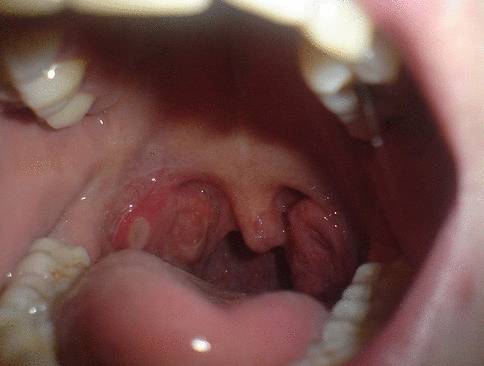

На начальном этапе развития онкологии горла визуальные проявления могут отсутствовать. Однако у пациенток возникают атипичные проявления, которые схожи с инфекционными поражениями горла. Рак горла, симптомы у женщин отличаются интенсивностью, имеет выраженный отек и покраснение слизистой оболочки. При рассмотрении новообразования под микроскопом можно наблюдать, что на поверхности опухоли располагаются папилломообразные структуры.

Симптомы рака горла у женщин – фото